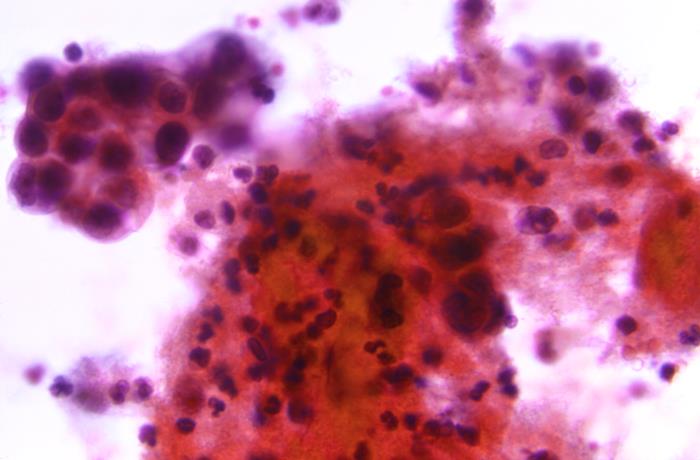

This photomicrograph of a Papanicolaou test, or Pap test, revealed findings indicative of a positive result for the presence of uterine cervical adenocarcinoma, classified as Stage-III.